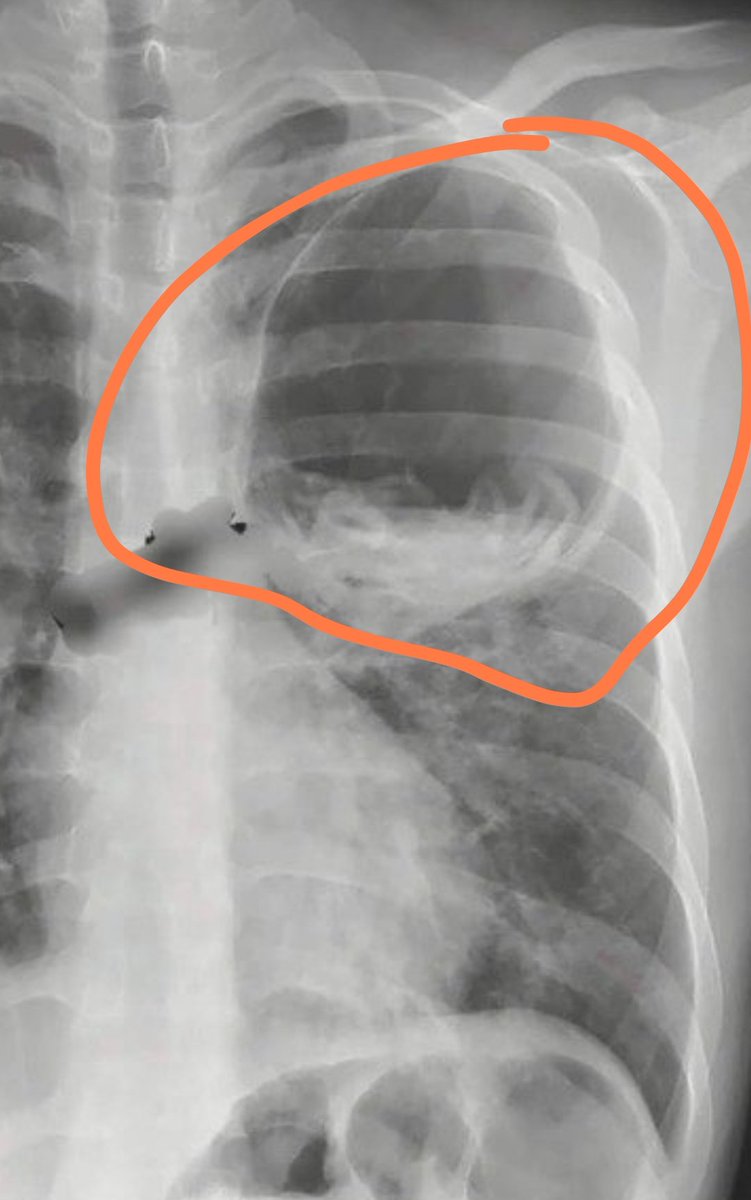

التشخيص المحتمل؟

هذه العلامة مميزة لمرض ما ..🪷

لن تنسوها بعد هذه التغريدة